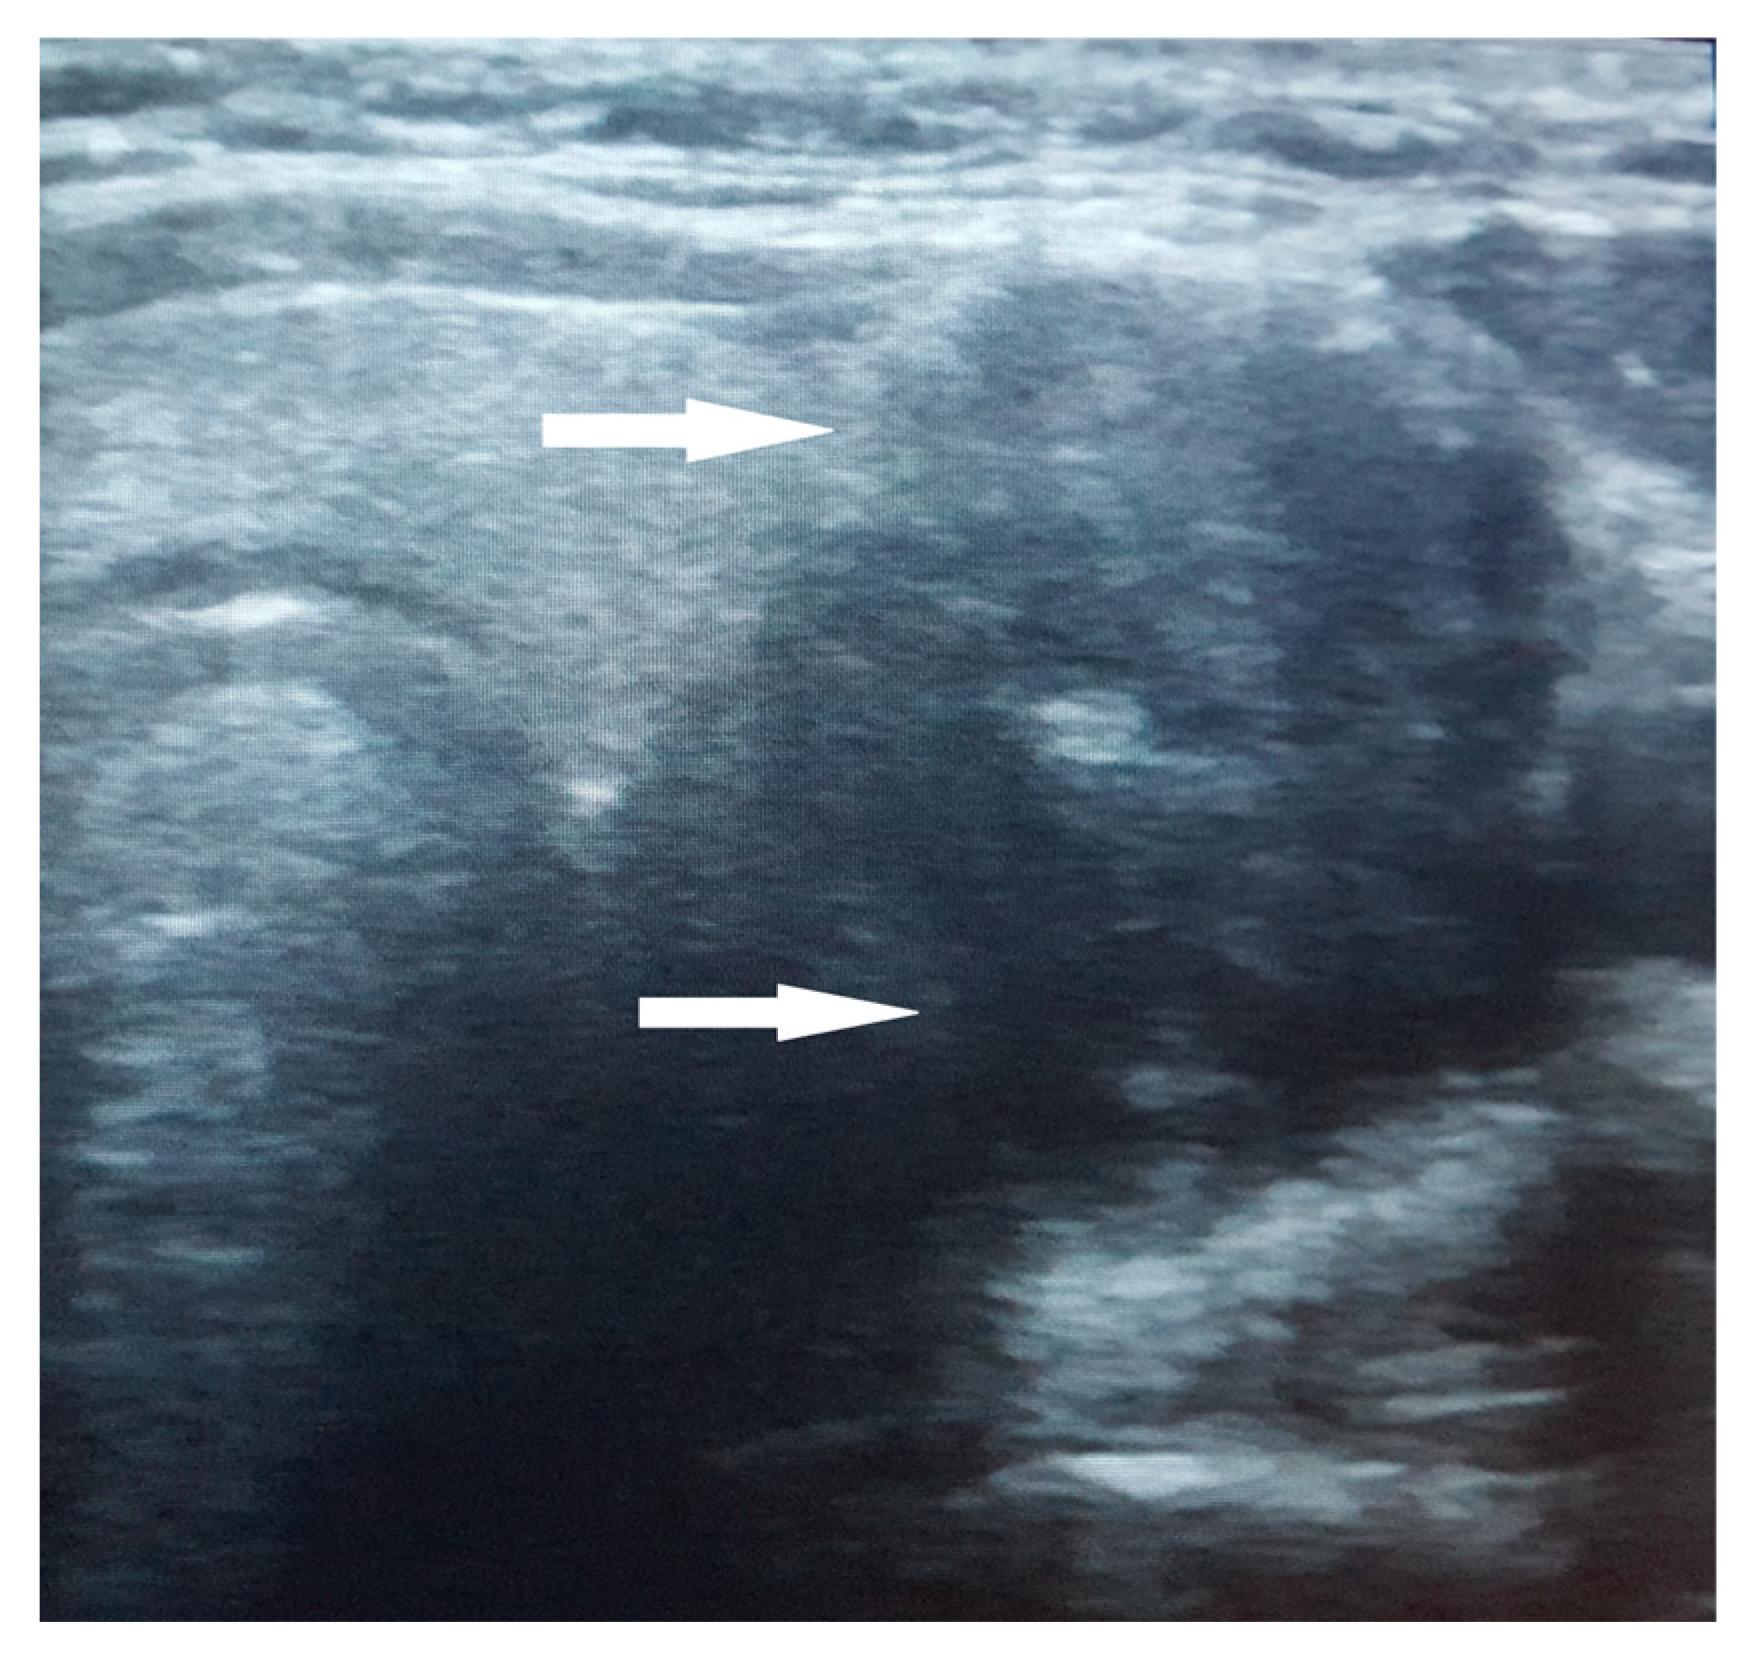

2.3. Biological and Paraclinical Assessment